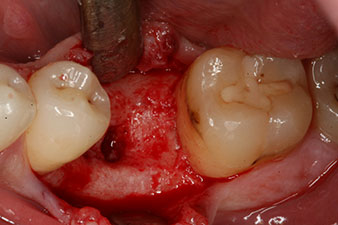

Sechs Wochen nach Extraktion zeigte sich jedoch nach Präparation des Mukoperiostlappens im Bereich der ehemaligen mesialen Alveole eine unvollständige Ossifikation.

Nach gründlicher Entfernung des Granulationsgewebes wurde das Implantat wie geplant eingebracht (blueSky, bredent).